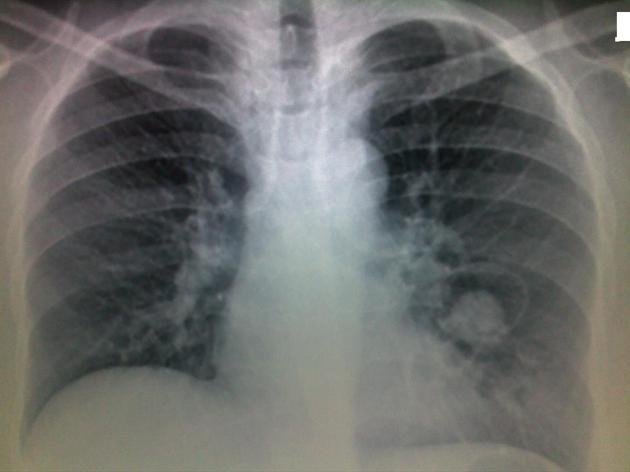

Finger in glove x ray sign

X ray - aspergilloma - opacity with a hole